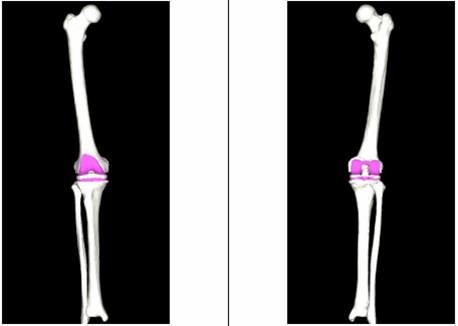

术前:

(图一)通过AIJOINT进行术前精准定位

(图二)模拟截骨后假体安放

(图三)IPSI:智能患者个性化导板

(图四)带位点标记的患者膝关节3D模型